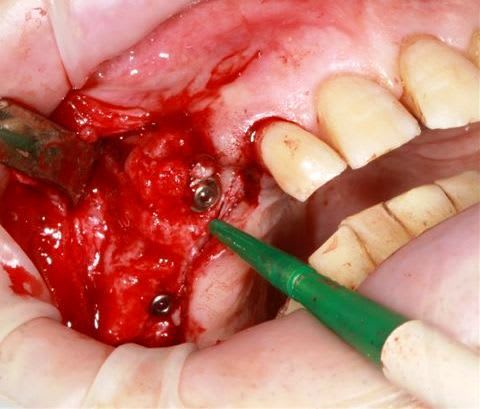

Ensuite zone 16 .. carottage, sciage en vest, carottage prélèvement de la carotte ajustage (délicat ça glisse:-)))

modelage zone 13,finitions, mise en place du bloc osseux, qui sera soigneusement impacté (pas de vis) prélèvement d'un petit bloc triangulaire pour finir la fermeture, éponges de gelatemp, sutures.